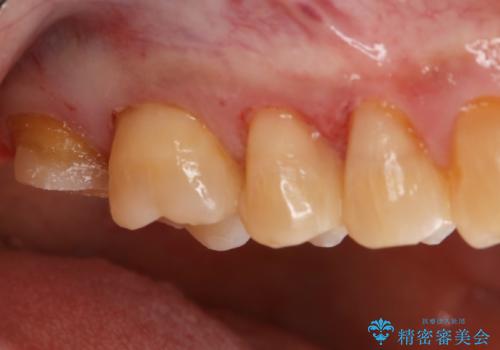

オールセラミッククラウン

金属を一切使わずセラミックのみで構成されており、自然な色調を再現することに長けた被せ物をオールセラミッククラウンといいます。

以前は耐久度(割れにくさ)の点で不安があるといわれていましたが、人工ダイアモンドとも呼ばれる『ジルコニア』の加工技術が向上してきたことにより、より精密で高強度の被せ物が製作されるようになりました。

ジルコニアで補強したベースの上に細かな色調が再現できる陶材を築盛することで周りの歯と調和した色調の被せ物の作製が可能となっています。